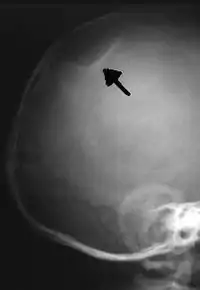

The material factual allegations of the amended complaint are as follows. Plaintiff was born on May 14, 1970. On repeated occasions during the first year of her life she was severely beaten by her mother and the latter's common law husband, one Reyes. On April 26, 1971, when the plaintiff was eleven months old, her mother took her to the San Jose Hospital for examination, diagnosis, and treatment. The attending physician was defendant Dr. Flood, acting on his own behalf and as agent of the defendant San Jose Hospital. At the time, the plaintiff was suffering from a comminuted spiral fracture of the right tibia and fibula, which gave the appearance of having been caused by a twisting force. Plaintiff's mother had no explanation for this injury. Plaintiff had bruises over her entire body. In addition, she had a non-depressed linear skull fracture which was then in the process of healing. Plaintiff demonstrated fear and apprehension when approached. Inasmuch as all plaintiff's injuries gave the appearance of having been intentionally inflicted by other persons, she exhibited the medical condition known as the battered child syndrome.

It is alleged that proper diagnosis of plaintiff's condition would have included taking X-rays of her entire skeletal structure, and that such procedure would have revealed the fracture of her skull. Defendants negligently failed to take such X-rays, and thereby negligently failed to diagnose her true condition. It is further alleged that proper medical treatment of plaintiff's battered child syndrome would have included reporting her injuries to local law enforcement authorities or juvenile probation department. Such a report would have resulted in an investigation by the concerned agencies, followed by a placement of plaintiff in protective custody until her safety was assured. Defendants negligently failed to make such report.

On this appeal plaintiff has expressly abandoned her claim of punitive damages. It is alleged that proper diagnosis of plaintiff's condition would have included taking X-rays of her entire skeletal structure, and that such procedure would have revealed the fracture of her skull. Defendants negligently failed to take such X-rays, and thereby negligently failed to diagnose her true condition. It is further alleged that proper medical treatment of plaintiff's battered child syndrome would have included reporting her injuries to local law enforcement authorities or juvenile probation department. Such a report would have resulted in an investigation by the concerned agencies, followed by a placement of plaintiff in protective custody until her safety was assured. Defendants negligently failed to make such report. The complaint avers that as a proximate result of the foregoing negligence plaintiff was released from the San Jose Hospital without proper diagnosis and treatment of her battered child syndrome, and was returned to the custody of her mother and Reyes who resumed physically abusing her until she sustained traumatic blows to her right eye and back, puncture wounds over her left lower leg and across her back, severe bites on her face, and second and third degree burns on her left hand.